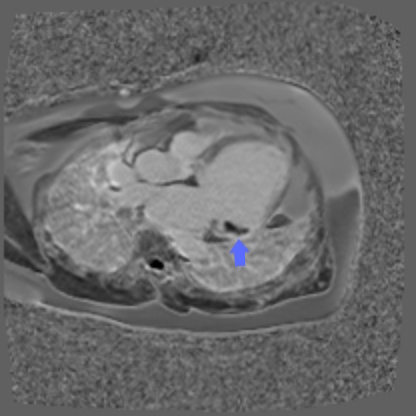

A 54-year-old Spanish-speaking male with no past medical history presented after being found unconscious and diaphoretic. Electrocardiogram demonstrated sustained monomorphic VT. After stabilization, transthoracic echocardiography revealed a left ventricular (LV) ejection fraction 30-35% with global hypokinesis and severely dilated LV cavity. Coronary angiography revealed patent coronaries. Further workup with cardiac magnetic resonance imaging demonstrated transmural late gadolinium enhancement in the basal to mid-lateral wall corresponding with hypokinetic myocardium, with a LV thrombus adjacent to the mitral valve and developing apicolateral aneurysm. An 18-fludeoxyglucose positron emission tomography scan was done which showed increased glucose uptake in the dysfunctional mid-lateral to apicolateral and anterolateral myocardium, without extracardiac evidence of sarcoid. Serologic testing was notable for an initially positive Lyme IgM, but confirmatory testing was negative. Further, serologies for Trypanosoma cruzi returned positive.